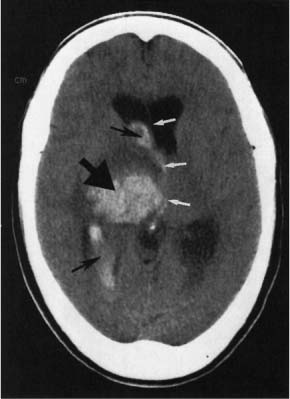

The CT scan showed a hemorrhagic stroke with bleeding in the right basal ganglia (large black arrow) and into the ventricles (small black arrows). (The white arrows illustrate midline shift.)

As is true for ischemic strokes, the main risk factor for hemorrhagic strokes is hypertension. In hemorrhagic strokes, it is important to not aggressively lower blood pressure. Some authorities recommend lowering blood pressure only when mean arterial pressure (MAP) is >130 mm Hg. After the hemorrhagic stroke is over, blood pressure should be treated aggressively. Modest decreases in blood pressure (12/5 mmHg) from one of many classes of hypertensive drugs lower recurrent stroke risk by 50% to 75%.